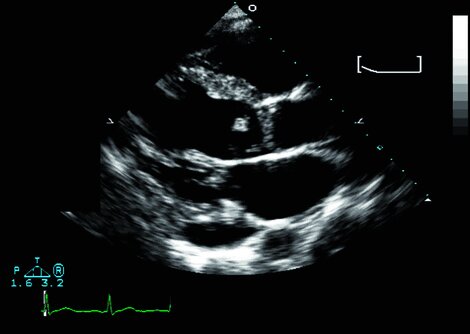

Echokardiographie und Mikrobiologie (siehe „Labor") sind die Eckpfeiler der Endokarditis-Diagnostik.

Drei echokardiographische Befunde gelten als Hauptkriterien der infektiösen Endokarditis:

• Vegetationen

• (Herz-)Abszess

• Neue Dehiszenz einer Klappenprothese

Außer der Echokardiographie kommen weitere bildgebende Verfahren wie Herz-CT und 18F-FDG-PET/CT zum Einsatz. In der Sonographie kann eine Splenomegalie auffallen (in ca. 30%) und evtl. Organinfarkte oder Abszesse.